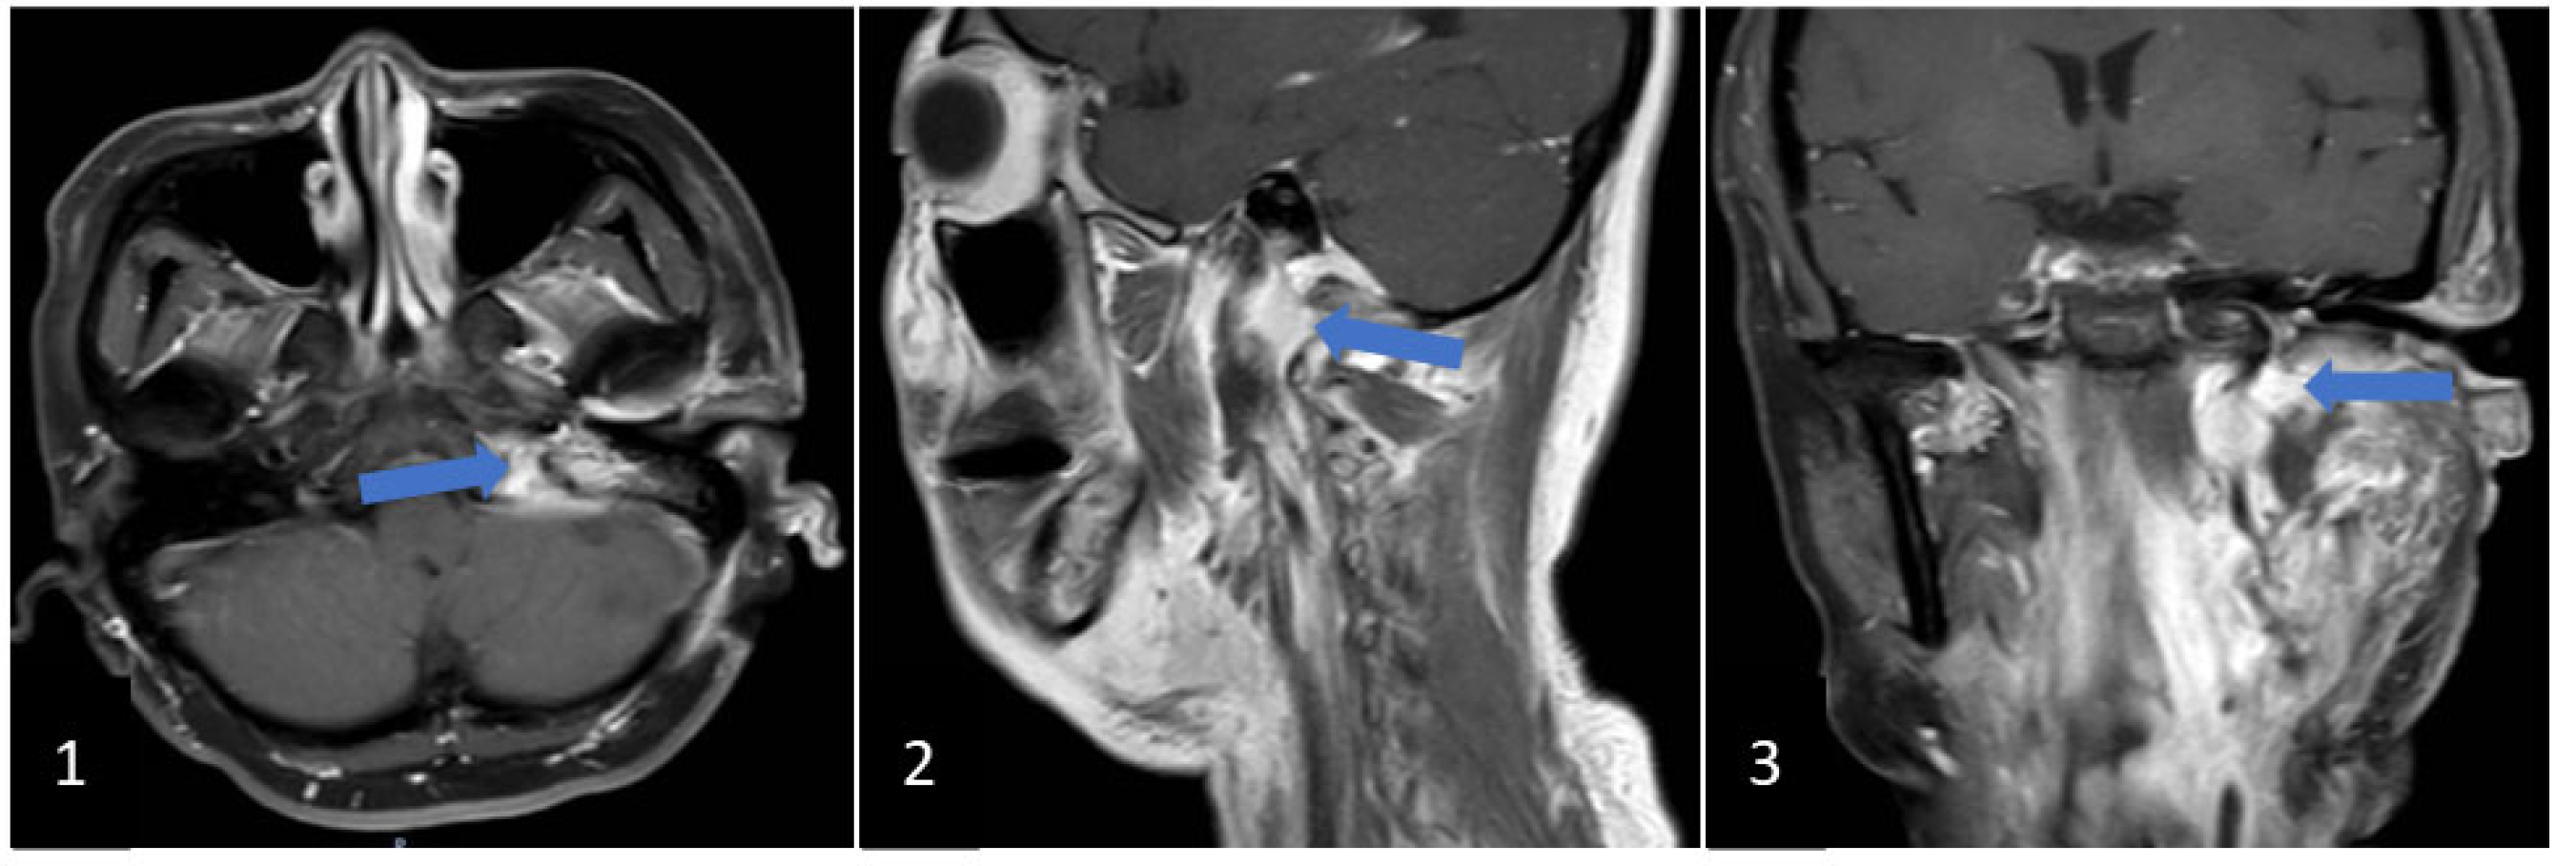

2. Clinical Case